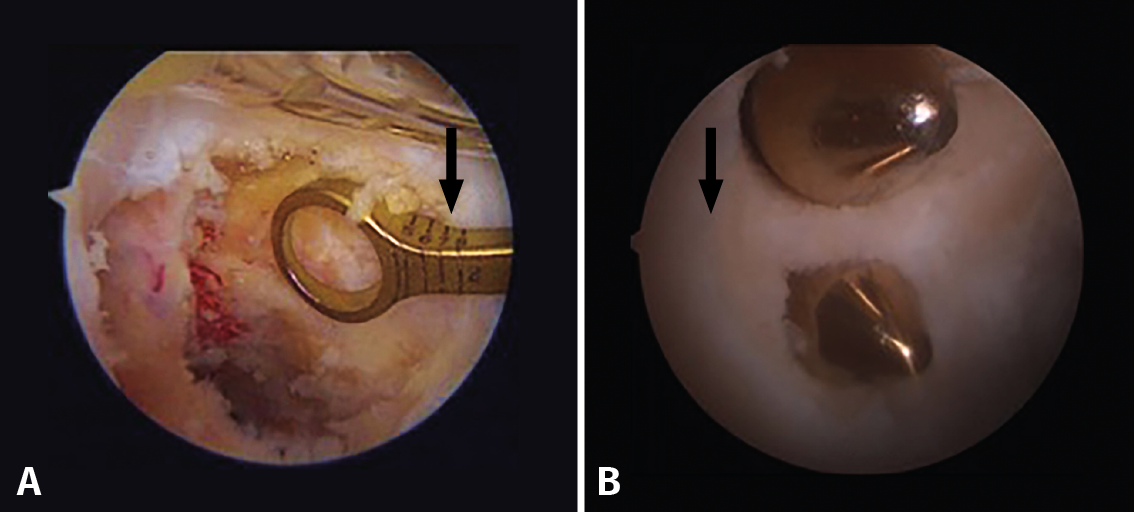

Femoral tunnel

Two anatomical references have been described that indicate the location of the insertions of the two PCL bundles in the femur: the most distal point of the centre of the trochlear groove (the trochlear point) and the midpoint of the intercondylar arch at internal femoral condylar level (the medial arch point), delimiting the AL bundle that ends its distal insertion precisely at subchondral level. The PM bundle in turn is located more dorsal and proximal to that point (about 10 mm from the chondral margin)(27).

In the case of single bundle reconstructions, we should seek to position the tunnel at the centre of the two original insertion sites, with a slight tendency to reproduce the AL bundle, which is anatomically more consistent and mechanically more resistant. In the case of double bundle reconstructions, the originally described technique contemplates an 11-mm tunnel at the level of the AL bundle insertion site and a 7-mm tunnel at the PM bundle insertion site, leaving a minimum 2-mm bone bridge between the two of them (Figure 11)(28).

Figure 11. A: single bundle reconstruction. The outside-in drilling guide indicates how many millimetres the femoral tunnel is being positioned from the chondral margin (arrow); B: double bundle reconstruction. Note the distance from the chondral margin (arrow) and the bone bridge between the two tunnels.